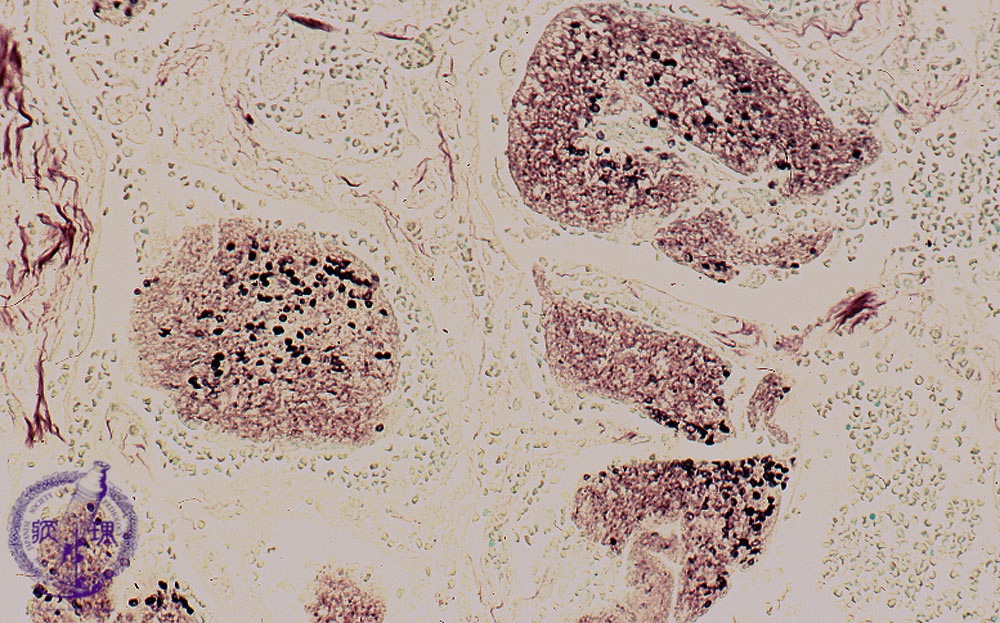

Microscopic view (Grocott stain, intermediate power view): On Grocott stain capsules of pneumocystis are round, cup or crescent shaped and 5 to 7um in diameter (smaller than an erythrocyte).